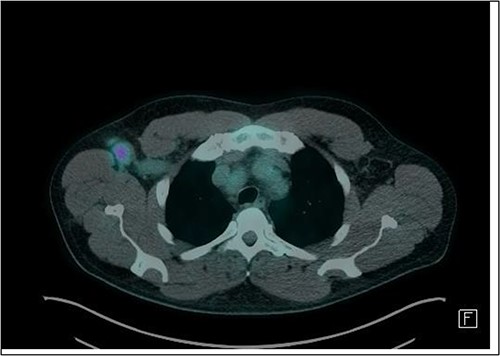

Given the histologic finding of an EBER-ISH+ lymphoid population coupled with pancytopenia, hyperuricaemia and elevated serum LDH, we favoured a provisional diagnosis of polymorphic PTLD. This was seemingly validated by PET scanning, which demonstrated FDG avidity in multiple right axillary lymph nodes (Fig. 3).

Axial slice of FDG-PET CT scan showing a 22 mm (short-axis) moderately FDG-avid right axillary lymph node (SUV-max 4.19).